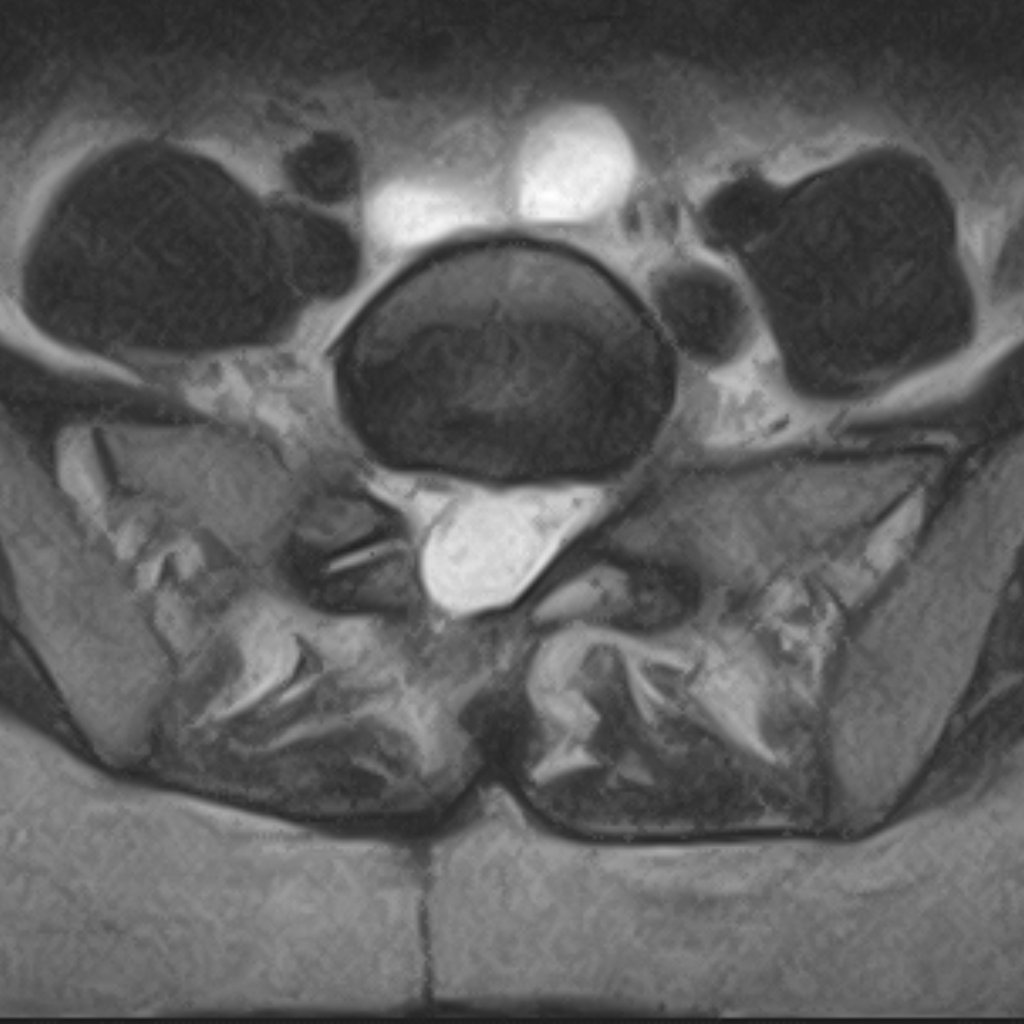

RMN: hernie de disc lombară — materialul discal comprimă rădăcina nervoasă

Hernie de disc lombară

Hernia de disc lombară cauzează de obicei durere iradiată în picior, amorțeală și slăbiciune musculară. Examinarea RMN este necesară pentru diagnostic precis.